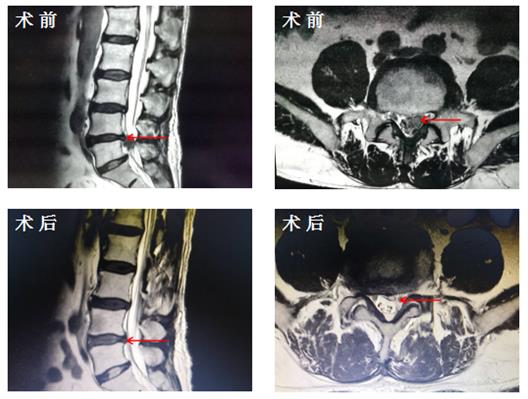

骨科成功完成我院首例经椎间孔镜下腰椎间盘摘除术

近日,我院骨科成功为一位腰椎间盘突出症患者实施了经椎间孔镜下腰椎间盘摘除术,完成了我院首例微创手术治疗腰椎间盘突出症,填补了我院骨科微创手术的另一个空白。患者张某,男,68岁。退...